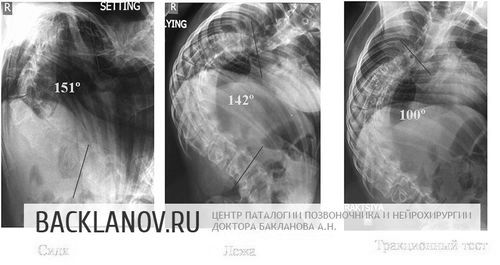

У нього складне захворювання хребта на тлі дегенеративного захворювання нервової системи, що викликало формування важкого грудо-попереково-крижового сколіозу в 151˚.

Рената Муртазіна, 17 років. Діагноз юної Ренати Муртазін - спінальної-м'язова амиотрофия Верднига-Гофмана, з грубим лівостороннім нейромускулярним грудо-поперекового сколіозом 130˚.